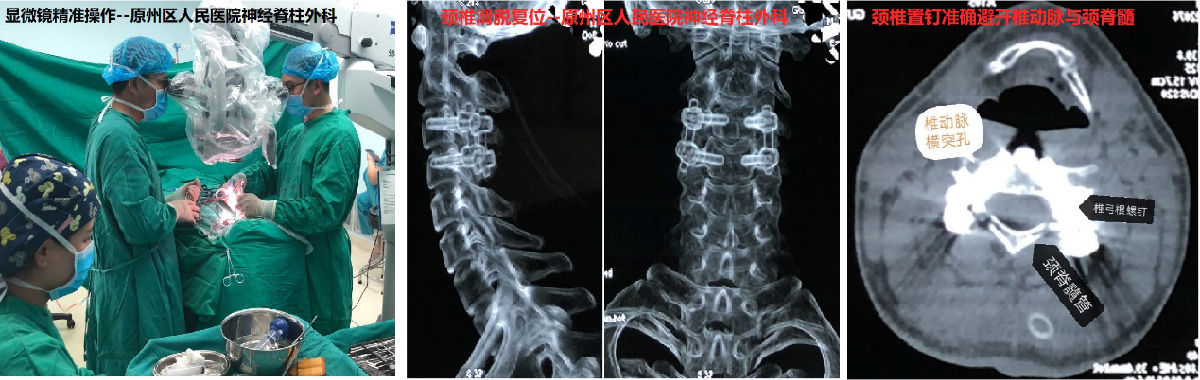

鄭小斌介紹,頸椎椎弓根直徑較小,外緣毗鄰椎動脈,內緣即頸脊髓手術中對椎弓根置釘的準確性要求非常高,否則容易造成癱瘓或腦干、小腦梗死以及大出血等風險,甚至在手術臺上即出現呼吸、心跳驟停的可能。于是他們采用了“顯微鏡技術”。此項技術可以在不過多破壞頸椎正常骨質的前提下,松解絞鎖的關節,可視化下探查并準確制備每個置釘通道,確保置釘精確性,通過椎弓根釘復位技術,縮短了頸椎的固定節段,也避免了聯合前路手術的需要。

經過3個多小時的手術,王先生推出手術室,神經脊柱外科的手術團隊“長長”舒了口氣。經過一周多的恢復,患者歪斜的“脖子”已經能擺正回來了,手臂與肩部的麻痛也緩解,順利的步行出院。